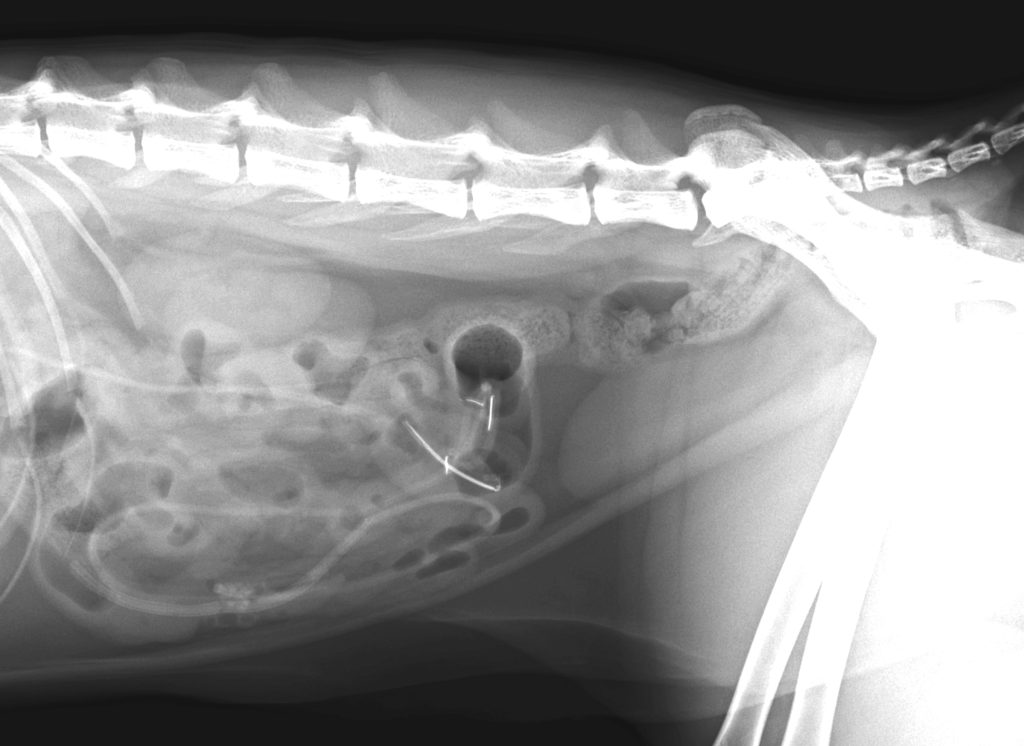

レントゲン検査を実施したところ、消化管内にコード状の異物が確認された。(電機関連のコードという印象ではなかった。)

異物がひも状であるということと、すでに異物は小腸内に達していたため、内視鏡の適応ではない。

胃・十二指腸・空腸・回腸の区間で異物が認められたため、それぞれ切開して異物を摘出した。

異物は主に一般的に女性が使用するヘアゴムで、そこに短いリボンニアヒモ、被毛が絡まっていた。